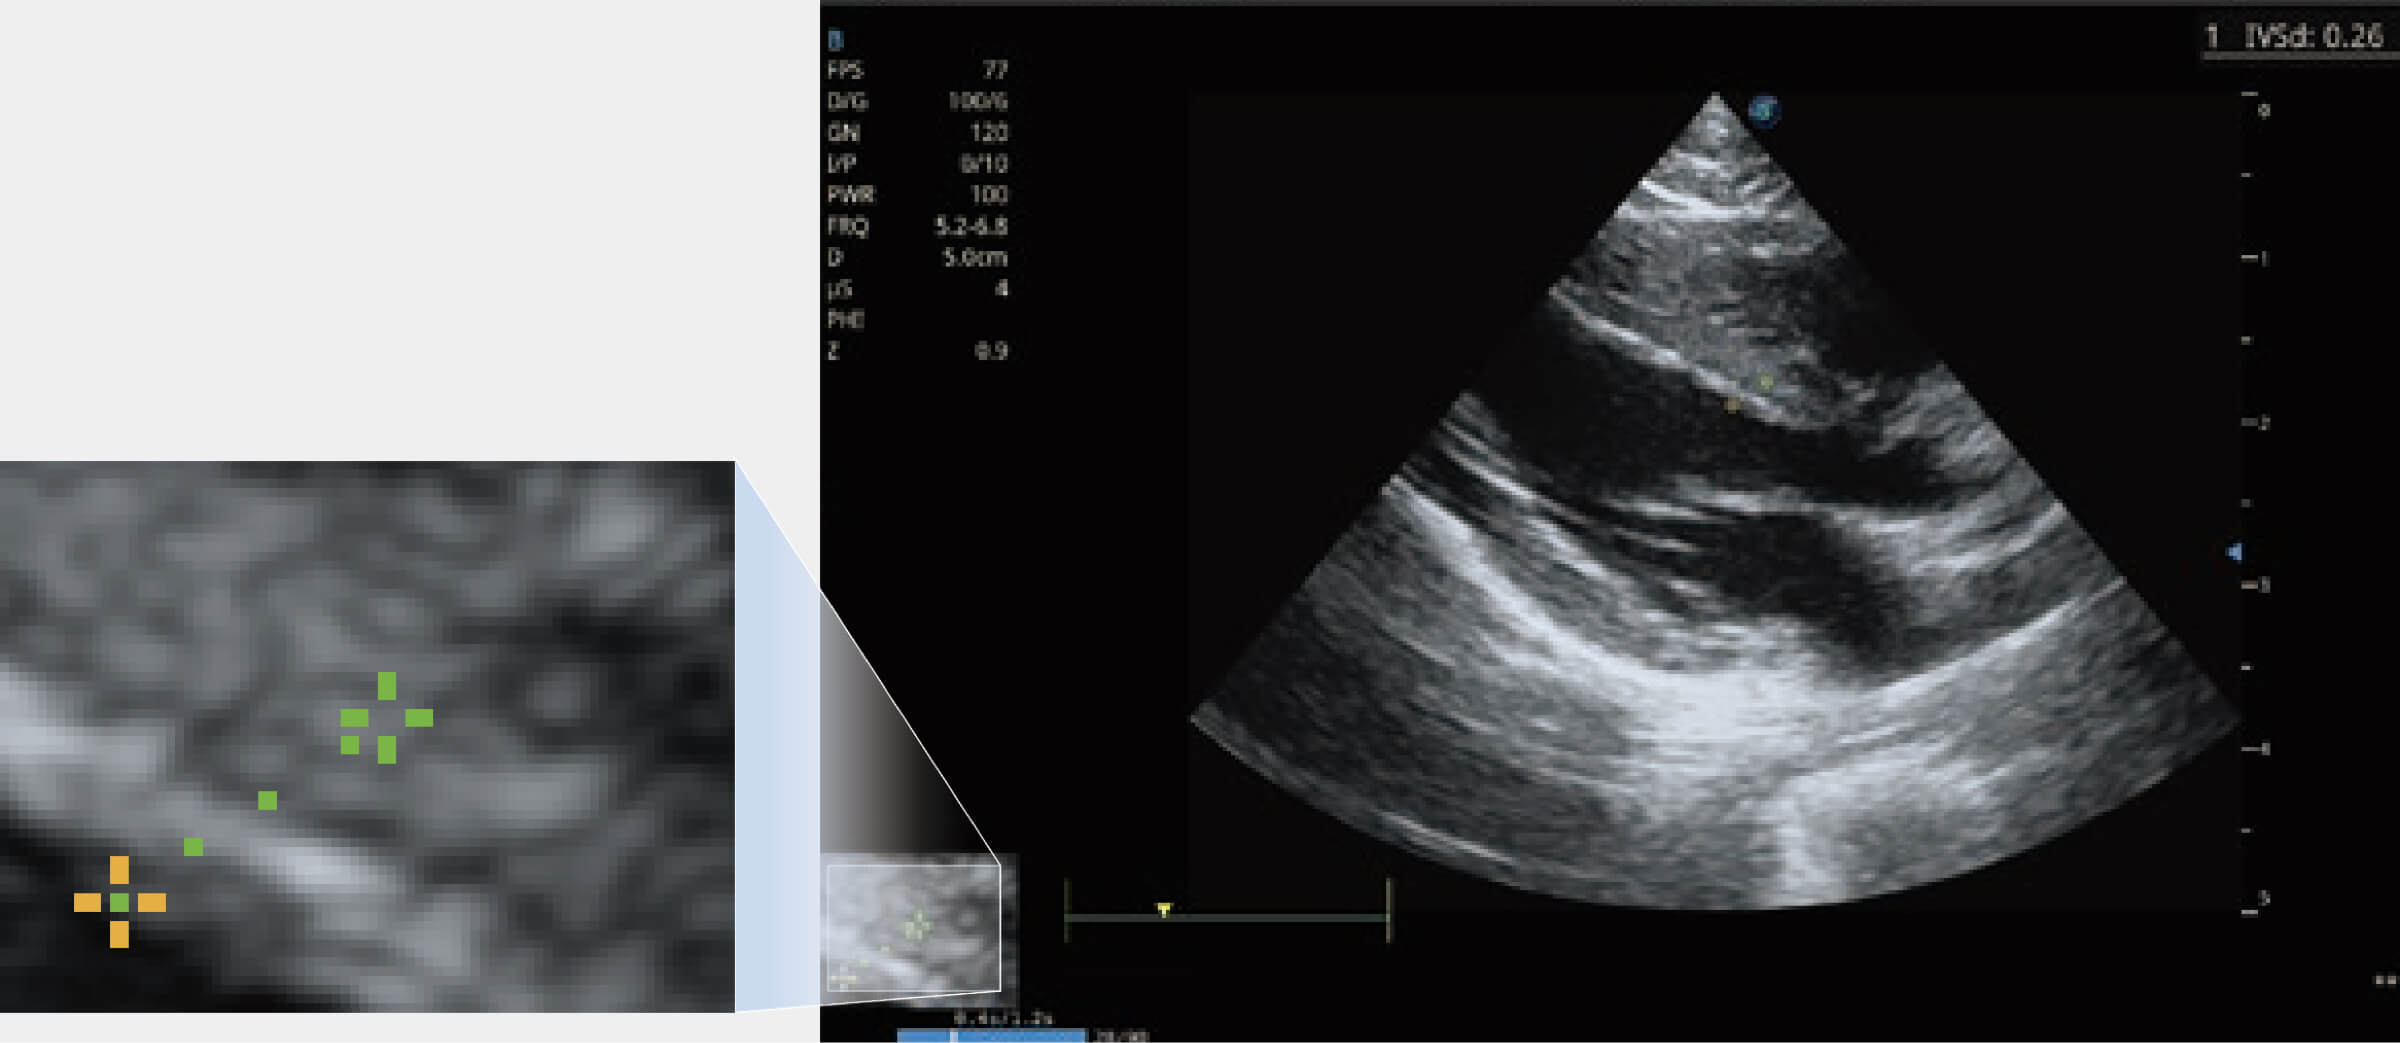

• Sono-Magnifier 測量放大器

為精細(xì)結(jié)構(gòu)及組織邊緣提供高清晰度的圖像和更大的成像視野。幫助減輕醫(yī)生的用眼疲勞,快速精準(zhǔn)獲得測量的數(shù)據(jù)。

(犬)四腔心MQA